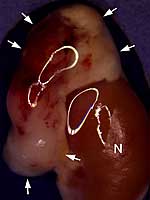

Bildunterschrift/Abbildungslegende: Der Niere (N) aufsitzender Tumor der Nebenniere (Pfeile) in einem genetisch modifizierten Mausmodell.

Bildquelle: AG Prof. Beuschlein